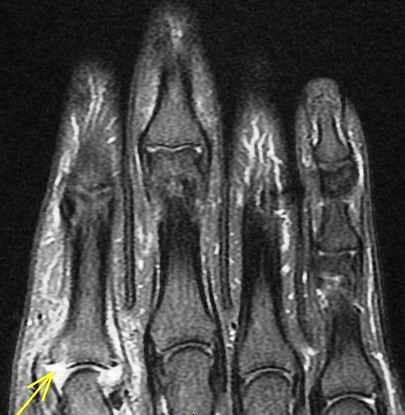

Figure 4 for case gout arthritis ( RID3567 )

Figure 4

Flexor tenosynovitis, tendon infiltration and also 2nd MCP synovitis with subtle reactive osteitis and early erosive change. My differential was RA vs gout. This is proven gout.